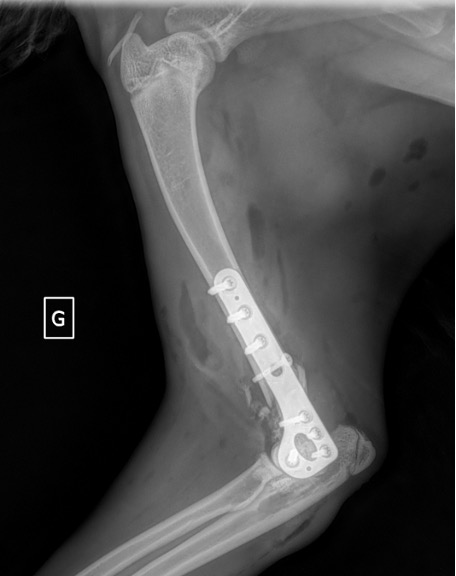

Exemple 2 :

Figure 4 : Pré-Op

Figure 5 : Post-Op Immédiat

Figure 6 : Post-Op 1 mois

Figure 7 : Post-Op 2 mois